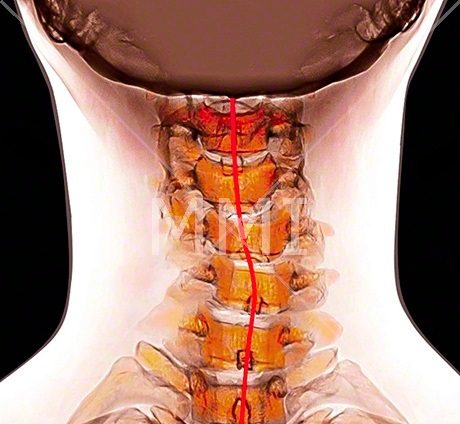

Шейно-грудной

Верхнегрудным, или шейно-грудным, называется сколиоз, при котором верхняя часть сколиотической дуги (угла сколиоза) располагается на уровне 4 и 5 грудных позвонков с распространением на шейный отдел. По мере прогрессирования патологии образуется компенсаторная дуга и в области пояснично-крестцового отдела.

Вдоль позвоночного столба расположены кровеносные сосуды и спинномозговые корешки. Последние иннервируют не только межпозвоночные диски, мягкие ткани, но и внутренние органы. Поэтому скручивание позвонков становится причиной снижения функциональной активности дыхательной, сердечно-сосудистой системы, ЖКТ. Для поражения сколиозом определенного отдела характерны свои специфические симптомы.

| Шейно-грудной | Шейно-грудное заболевание проявляется разным уровнем надплечий, кривошеей, деформацией костей черепа с асимметрией лица, выраженными головными болями. При его осложненном нарушением функцией спинного мозга течении наблюдается сильное искривление грудного отдела назад |